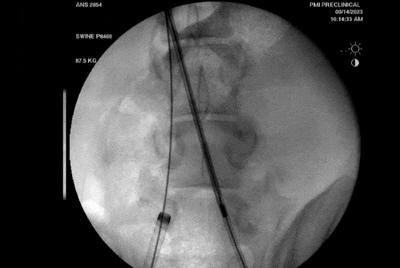

Recana支架內(nèi)旋切

同時(shí)在栓塞收集器近端設(shè)置一個(gè)錐形螺紋以及螺旋的金屬片,錐形螺紋能密實(shí)的血栓切削下來(lái),而螺旋的金屬片則可以清除大塊的血栓以及血管壁或者支架內(nèi)壁的血栓。因此Recana使醫(yī)生通過(guò)簡(jiǎn)單旋轉(zhuǎn)導(dǎo)管就能夠?qū)⒀芑蛘咧Ъ軆?nèi)血栓快速且干凈清除下來(lái)。